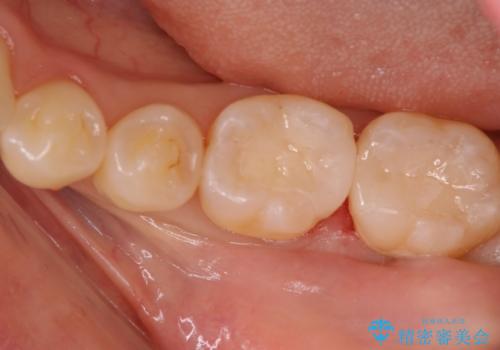

銀歯の治療も悪いわけではありませんが、残念なことに再治療になることがよくあります。

再治療しないためにも、いい型取りの材料を使用し歯の形に適した被せ物にすることをお勧めいたします。